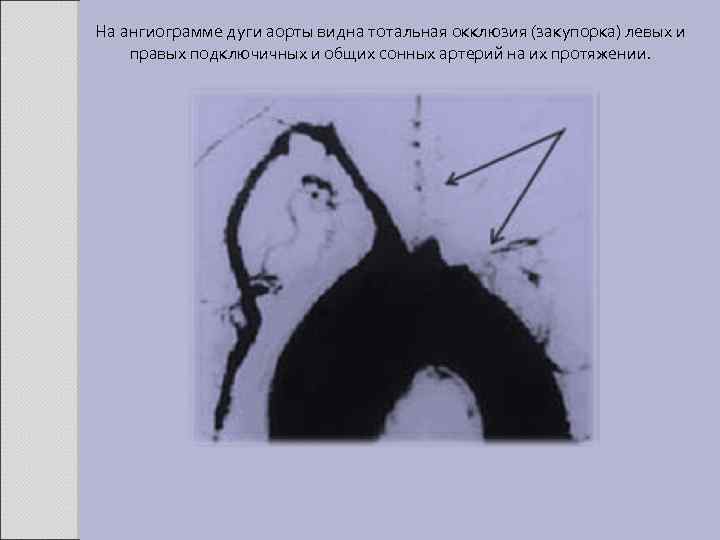

На ангиограмме дуги аорты видна тотальная окклюзия (закупорка) левых и правых подключичных и общих сонных артерий на их протяжении.

Физикальные данные: отсутствие пульсации (или её ослабление) ниже места окклюзии артерии, систолический шум над поражёнными сосудами (над подключичной артерией, брюшным отделом аорты). При поражении подключичной артерии можно выявить разницу АД на руках. Поражение почек. Следствие стеноза почечной артерии (чаще поражается левая почечная артерия). Возможно развитие гломерулонефрита, тромбоза почечных артерий. Очень редко наблюдают амилоидоз почек. Поражение лёгких. Лёгочная гипертензия возникает при неспецифическом аортоартериите IV типа, обычно в сочетании с какими-либо из перечисленных выше симптомов, реже - изолированно. Суставной синдром. Частое проявление - артралгии, более редкое - полиартрит, напоминающий ревматоидный. Поражение нервной системы. Неврологические расстройства возникают на фоне поражения левой (реже правой) общей сонной артерии, позвоночных артерий. Изредка у больных наблюдают обморочные состояния. Степень тяжести дисциркуляторной энцефалопатии коррелирует со степенью стеноза левой сонной артерии; при двустороннем сужении ишемия выражена максимально и может осложняться инсультами. При поражении позвоночных артерий характерны нарушения памяти, внимания и работоспособности, усиливающиеся по мере нарастания степени ишемии мозга.

Инструментальные методы обследования Аортография и селективная ангиография поражённых сосудов - наиболее информативные методы диагностики. Выявляют участки стеноза и постстенотического расширения, мешотчатые аневризмы, неполные и полные окклюзии ветвей дуги аорты, различные по локализации и протяжённости. Для наглядной визуализации артериальных стенозов применяют ультразвуковое сканирование сосудов. Диагностические критерии Американской ревматологической ассоциации • Возраст моложе 40 лет. • "Перемежающаяся хромота" верхних конечностей - быстрое развитие усталости и ощущение дискомфорта при работе руками. • Ослабление пульса на лучевой артерии, ослабление пульсации на одной или обеих плечевых артериях. • Разница систолического АД на правой и левой плечевых артериях более 10 мм рт. ст. • Систолический шум над подключичными артериями или брюшной аортой. • Ангиографические изменения: сужение или окклюзия аорты и/или её ветвей, не связанное с атеросклерозом, фибромускулярной дисплазией или другими причинами. Изменения обычно локальные или сегментарные. Диагноз считают достоверным при наличии 3 критериев и более. Чувствительность 90, 5%, специфичность 97, 8%.